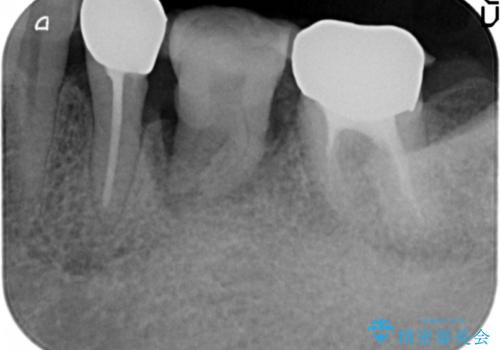

保存不可能な奥歯(左下6)を抜歯し、機能していない親知らず(左下8)の移植を行いました。

移植後、生着を待って根管治療及び補綴修復を行いました。

機能していない親知らずを用いて咬合を回復することができ、喜んで頂けました。